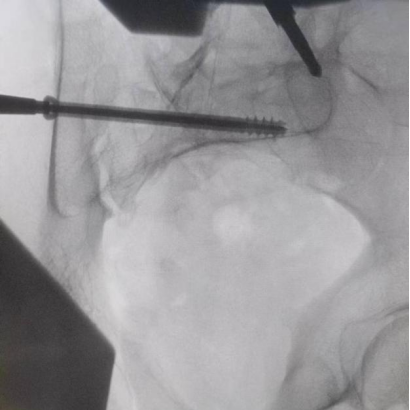

據(jù)了解,患者37歲,為高墜傷患者,入院合并顱腦挫傷、盆腔臟器出血、骨盆骨折多發(fā)傷患者。為最大限度降低手術(shù)風(fēng)險(xiǎn),同時(shí)給予患者滿意的手術(shù)療效,術(shù)前綜合評估患者病情,擬定行“天璣機(jī)器人”輔助定位下骨盆骨折微創(chuàng)手術(shù)。2月13日10時(shí),手術(shù)正式開始。拉薩市人民醫(yī)院采集患者術(shù)中二維影像,通過骨科手術(shù)機(jī)器人擬定螺釘打入位置方向后,吳宏華主任完成手術(shù)設(shè)計(jì),成功為該患者置入了一顆高難度骶髂螺釘,出血5ml,切口1cm。術(shù)后圖像顯示,螺釘位置及方向完全符合手術(shù)規(guī)劃,沒有一絲偏差,手術(shù)最終獲得圓滿成功。

圖為透視下見置入的骶髂螺釘,位置、長度精準(zhǔn),無絲毫偏差